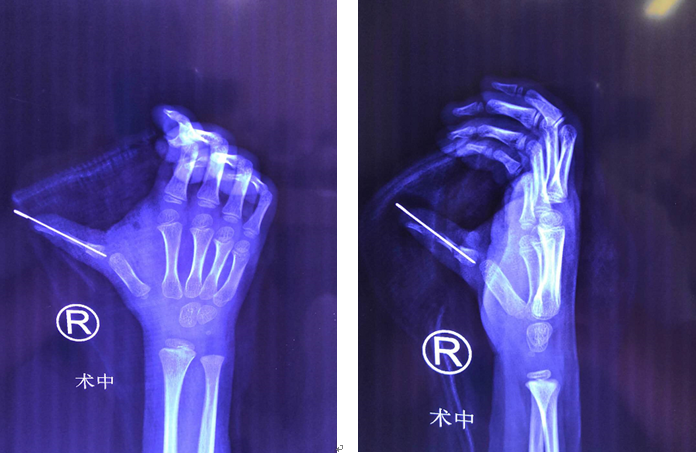

浩浩的主治醫(yī)生,徐州仁慈醫(yī)院手外科朱輝主任介紹,“這個孩子右手比較特殊,兩根拇指,一個外形長的好看沒有功能,一個功能比較好但沒有指甲。單純留哪一個都不完美,合并在一起,才能成一個較接近正常的手指。這既需要相當?shù)募夹g(shù)做保證,也需要骨骼發(fā)育到一定程度才能做手術(shù)。”

在遵守基本原則的前提下,朱主任、滕道練醫(yī)生團隊針對浩浩的右手情況,做了個性化的手術(shù)設計,采取微創(chuàng)切口、術(shù)后美容線精細縫合的方式,在拇指功能良好的基礎上,確保術(shù)后無明顯疤痕。